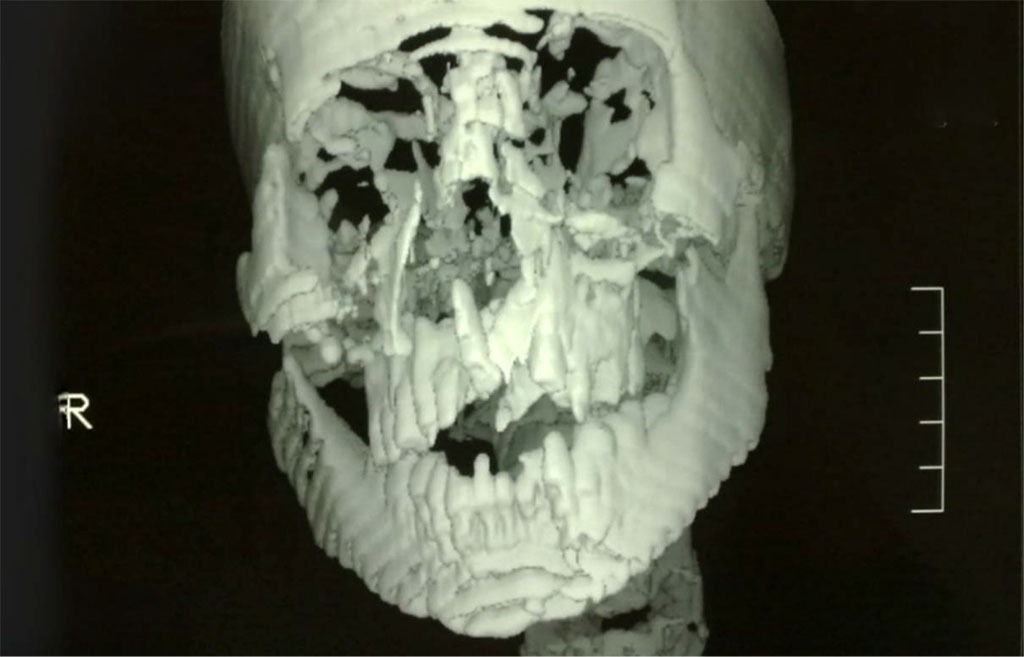

Cranio-facial Multidetector Computerized Tomography (MDCT) confirmed our diagnosis, excluded other fractures, intracranial lesions, cerebral oedema and hemorrhage [Figure 2,3]. The patient was given one gm I.V. CefotaximeTM. The decision was made for closed reduction (except for the mandibular fracture) under general anathesia with nasal intubation.

Figure 2: MDCT showing the maxillary Le Fort I and the left parasymphysial mandibular fractures.

Figure 3: MDCT showing the maxillary Le Fort I and the left parasymphysial mandibular fractures.